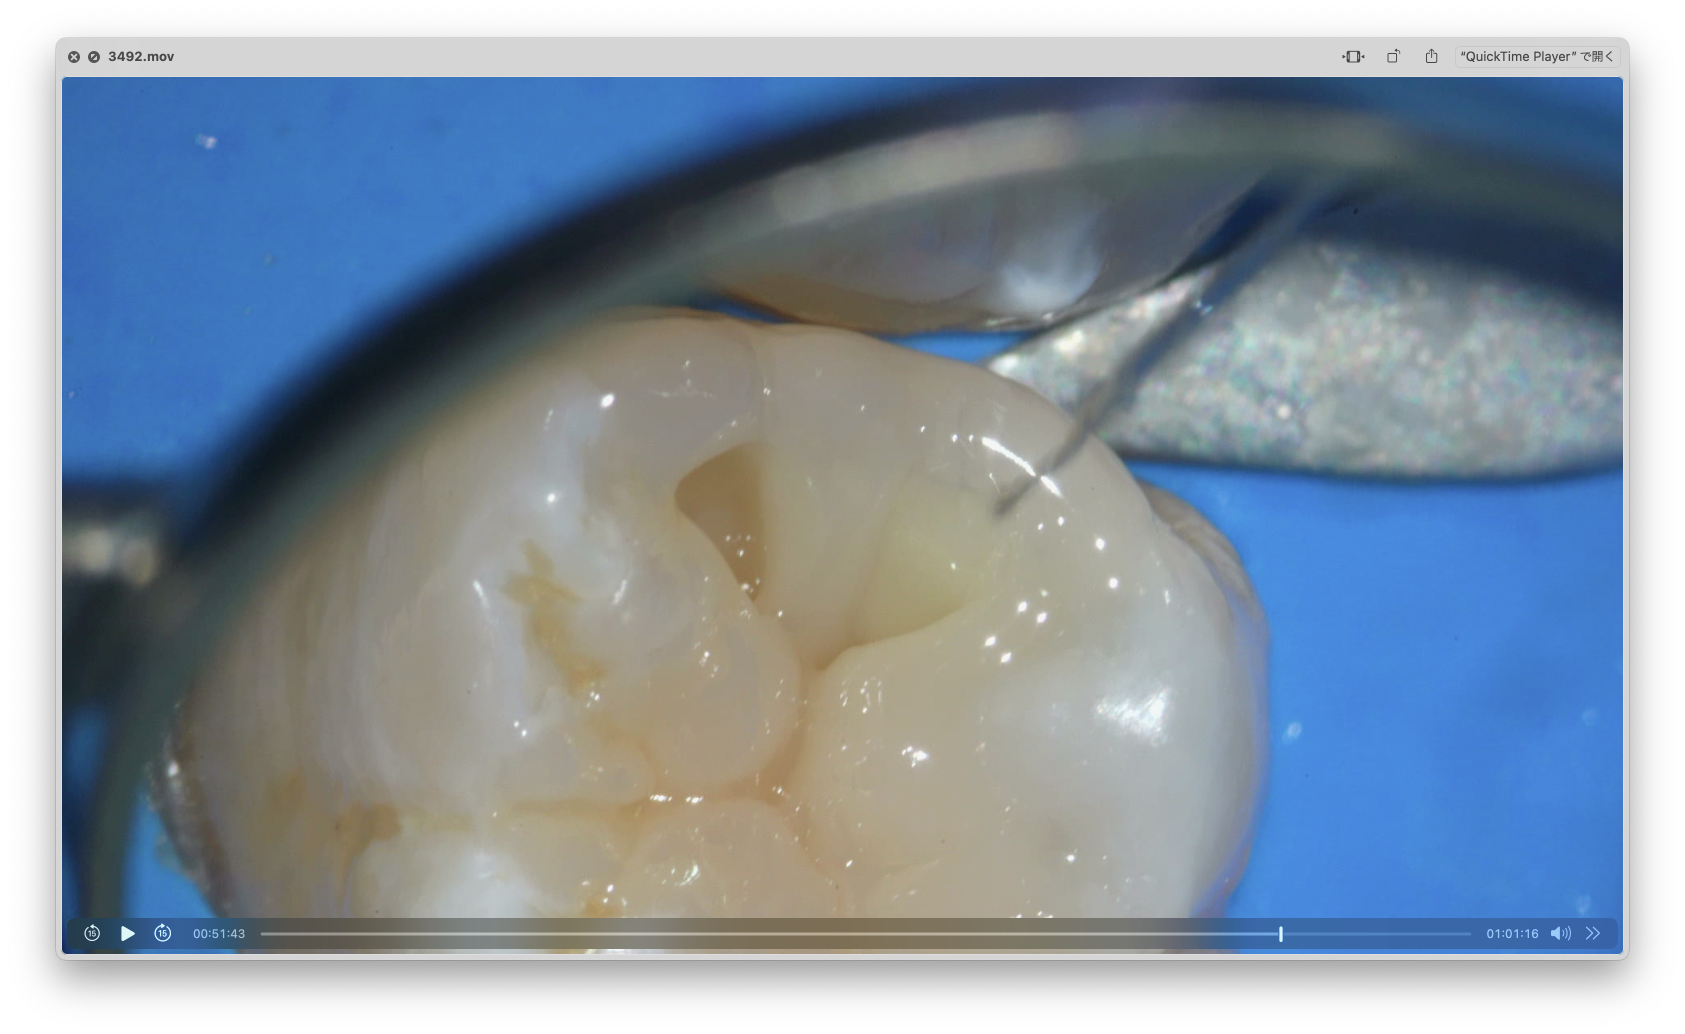

顕微鏡下で歯の構造を解剖学で再現していくのですが、とても細かく技術がいるものです。

最初の金属の溝に注目して頂きたいのですが、

凹凸がなく平坦な形をしていますよね。

そこから歯の山と谷を作る作業をしていきます。

実はこの山と谷は噛み合わせにおいて重要な役割をします。

ここでいう噛み合わせは、食べのもの消化や顎の動き、歯への負担に関わってきます。